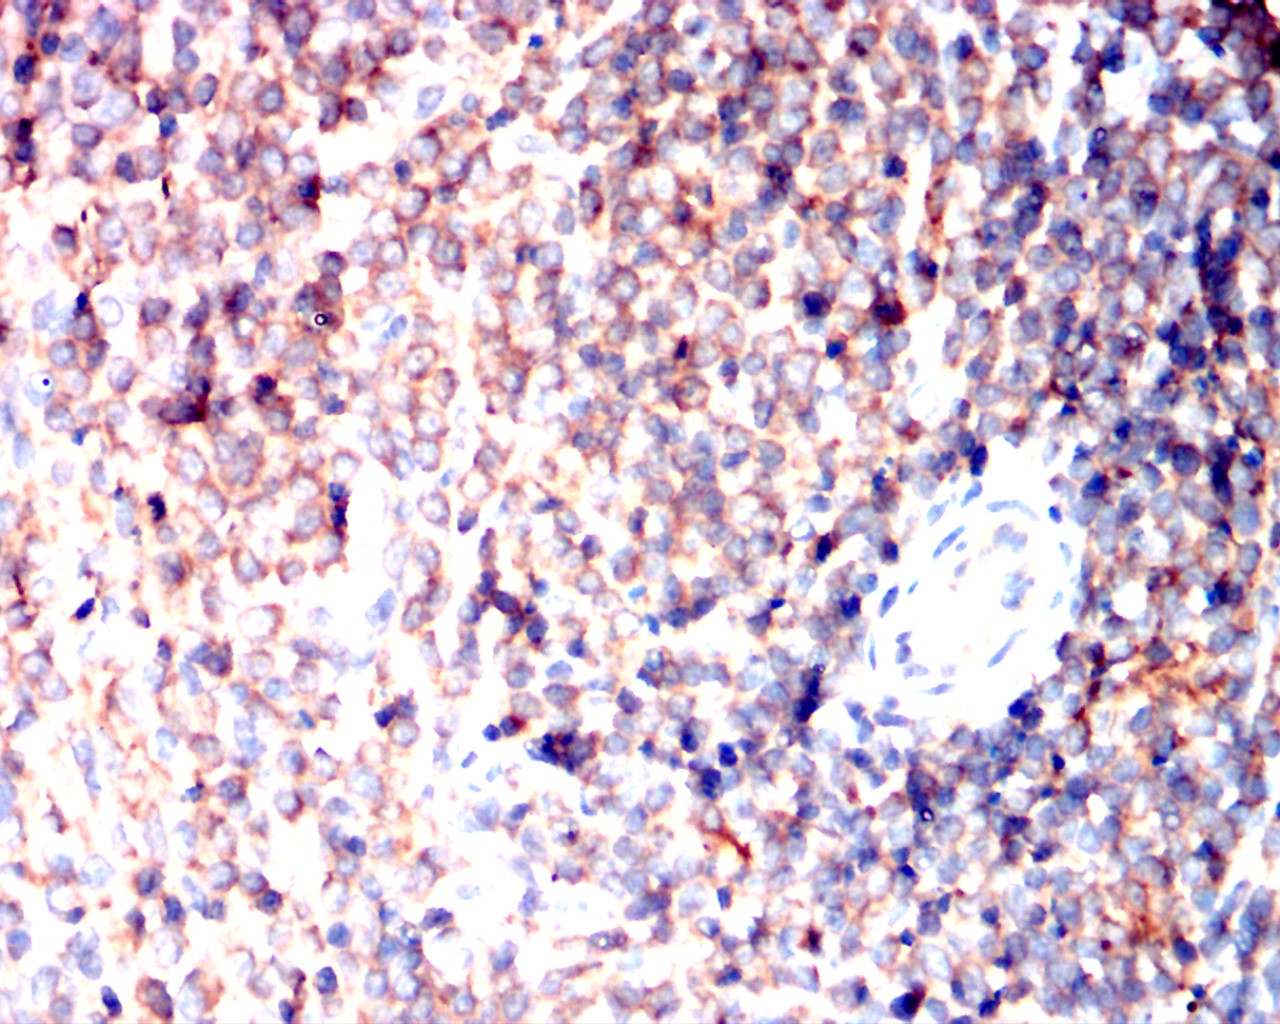

Immunohistochemical analysis of paraffin-embedded mouse spleen showing cytoplasmic localization using PIK3CA mouse mAb with DAB staining.

Immunohistochemical analysis of paraffin-embedded rat spleen showing cytoplasmic localization using PIK3CA mouse mAb with DAB staining.

Immunohistochemical analysis of paraffin-embedded rabbit spleen showing cytoplasmic localization using PIK3CA mouse mAb with DAB staining.